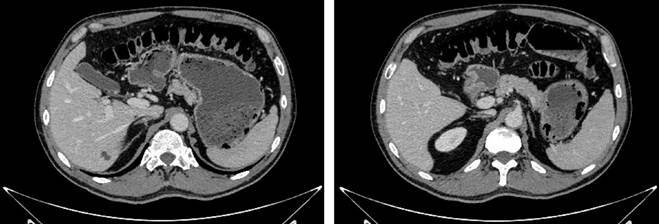

We present the case of a 62-year-old male patient who arrived at the emergency department with a three-day history of abdominal pain and distension, multiple episodes of diarrhea without gastrointestinal bleeding, nausea, vomiting, and fever. The patient attributed these symptoms to the consumption of spoiled meat. Upon admission, his vital signs were within normal limits. Physical examination revealed abdominal distension and tenderness on palpation, but there were no signs of peritoneal irritation. Analgesia was administered, and laboratory tests were performed, showing normal leukocyte levels (8,700), mild neutrophilia (85%), elevated C-reactive protein (4.9), normal renal function, and adequate electrolytes and acid-base status. Due to persistent pain, an abdominal and pelvic computed tomography (CT) scan was ordered. The axial CT scan revealed gas bubbles, predominantly in the region corresponding to the hepatic dome and the left hepatic lobe, suggestive of portal venous gas (Figure 1). There was also liquid and gaseous distension of the gastric chamber, with air dissecting the gastric wall, particularly at the fundus and along the greater curvature (Figure 2), findings consistent with gastric wall pneumatosis and non-specific thickening of the gastric walls at the antropyloric region.